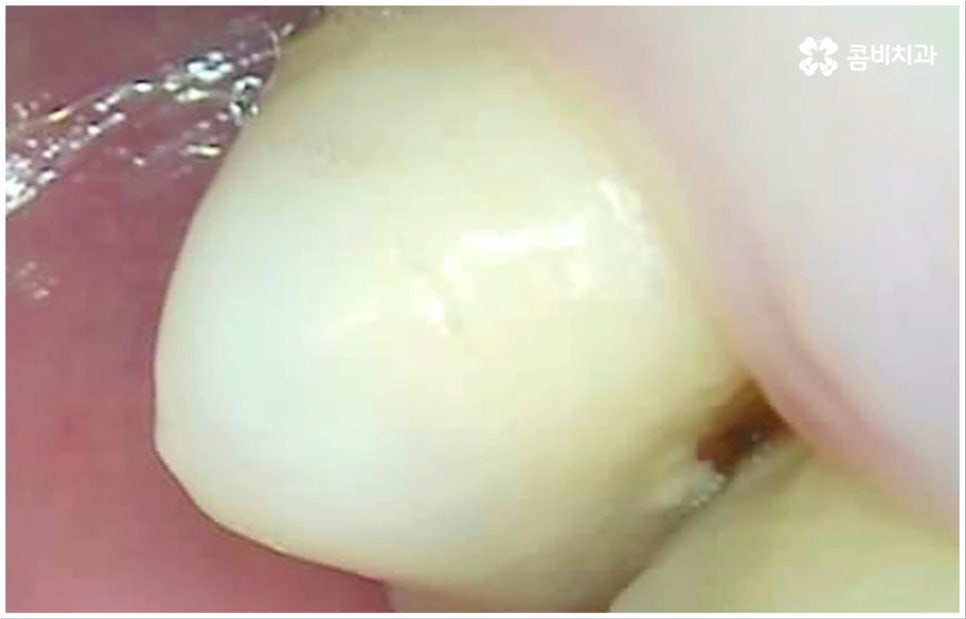

흔히 치과를 찾게 되는 원인 중 하나인 충치는 보통 위아래 치아가 맞닿는 교합면, 즉 우리가 식사를 할 때 음식물을 잘게 자르고 갈아주는 역할을 하는 씹는면에 발생할 가능성이 가장 크다고 할 수 있습니다. 그 이유는 교합면의 모양을 생각해 보면 잘 알 수 있는데요. 한 예로 우리가 거울 앞에서 입을 크게 벌렸을 때 쉽게 살펴볼 수 있는 아래 어금니의 교합면을 생각해 보면 윗면이 평평한 게 아니라 볼록하게 올라온 부위(교두)와 그 사이의 깊은 홈(구)으로 이루어져 있기 때문에 식사 후 치아 사이나 이 홈 부분에 음식물 찌꺼기나 침 등이 잔존할 가능성이 많은데, 이를 깨끗하게 제거해 주지 않으면 여기서 세균이 급증하여 충치 등 구강 질환이 발생할 빈도수도 높아지게 되는 거예요.

이러한 교합면 충치는 비교적 관찰이 쉽고 접근 역시 용이하기 때문에 조금만 주의를 기울이면 충분히 예방 또는 초기 치료를 할 수 있습니다. 물론 완전 초기 단계에서는 신경이 없는 치아 겉면인 법랑질부터 우식이 일어나기 때문에 충치 통증 도 거의 없고 육안으로 구별해 낼 수 있는 특징 (색깔 변화 등) 도 미미하므로 환자분들의 입장에서 충치가 발생했다는 것을 인지하기 어려울 수 있어요. 이와 같이 자기도 모르게 발생했을지 모를 충치에 대해 예방 및 조기 대처를 하기 위해서는 1년에 한 번 또는 두 번 정도 치과에 정기적으로 내원하셔서 꼼꼼하게 검진을 받으시는 것이 구강 건강을 지키기 위한 보다 바람직한 방법이 될 거예요.

여기서 우리가 더욱 주의를 기울여야 할 점은 병증이 조금 더 진행되어 자각 증상이 막 생겼을 때 시기를 놓치지 않고 바로 치료를 받아야 한다는 데 있어요. 이 때도 비교적 초기에 속하기 때문에 손상이 일어난 부위만 깨끗하게 삭제하고 레진으로 직접 때워주는 방식으로 치료할 수 있는 케이스가 대부분일 거예요. 물론 치료 내용은 자세한 상황에 따라 달라지겠지만 보통 약간 시리거나 찌릿하는 충치 통증 을 처음 느끼는 것은 법랑질 안 쪽의 상아질에 손상이 막 일어나기 시작하는 무렵이므로 이 시기에는 좀 더 빠르고 (보통 하루 만에 치료가 끝남) 간편한 직접 수복이 가능하기 때문에 환자분들의 입장에서도 의료진의 입장에서도 치료가 수월하며, 자연 치아의 삭제량이 적은 만큼 앞으로 관리를 잘 해 주면 해당 치아의 수명이 보다 길어질 수 있다는 점에서 구강 건강에 훨씬 유리하니 이 점을 유념하시고 치과 내원을 미루지 않으시길 권유드리고 있습니다.